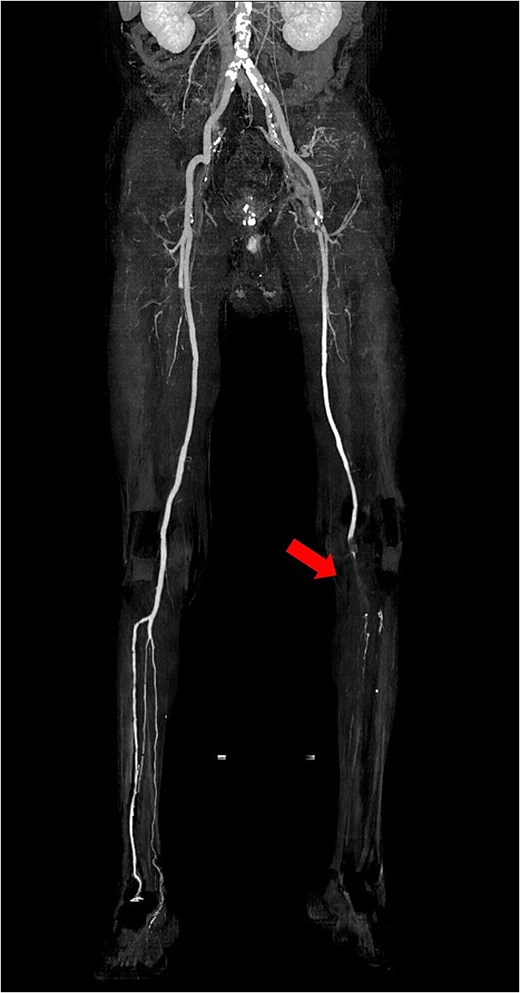

The patient was a 78-year-old man who had been hospitalized at a prior institution for Tolosa-Hunt syndrome, a rare inflammatory condition causing orbital pain. He had undergone steroid pulse therapy and was maintained on oral prednisolone (40 mg daily). He was also receiving medical treatment for diabetes mellitus, with an HbA1c level of 7.9%. The patient presented with complaints of left leg discomfort and weakness. Contrast-enhanced CT revealed poor perfusion distal to the left common iliac artery, leading to a diagnosis of ALI. He was subsequently transferred to our surgical department for further evaluation and treatment. On arrival, physical examination revealed coldness in the left lower limb, with absent palpable pulses in the dorsalis pedis and posterior tibial arteries. Doppler ultrasonography confirmed the absence of arterial flow in the left lower extremity, consistent with critical ischemia. The patient's electrocardiogram showed sinus rhythm. A review of CT imaging showed thrombotic occlusion extending from the left common femoral artery (CFA) to the superficial femoral artery, with poor perfusion distal to the popliteal artery (Video 1) (Fig. 1). Additionally, a filling defect was identified in the distal aortic arch, consistent with a thrombus (Fig. 2a). The thrombus appeared pedunculated and was attached to the lesser curvature of the descending thoracic aorta distal to the left subclavian artery. It was considered highly mobile, posing a significant risk of embolization. No evidence of intracardiac thrombi was observed, and the DTAT was identified as the likely embolic source responsible for the ALI. Given the urgency of salvaging the ischemic limb, thrombus retrieval was prioritized, while simultaneous management of the embolic source was deemed equally critical to prevent recurrence. Open surgery was considered high-risk due to the patient’s age, diabetes, and chronic steroid use. As a less invasive alternative, we opted for TEVAR to immobilize the floating thrombus. During the procedure, bilateral CFAs were surgically exposed to provide access and enable immediate removal of the embolic source if needed. A transesophageal echocardiogram (TEE) revealed a highly mobile intra-aortic thrombus (Video 2). A 26× 26 × 150 mm stent graft (Valiant Captivia Thoracic Stent Graft; Medtronic, Santa Rosa, CA, USA) was deployed just distal to the left subclavian artery under fluoroscopic guidance. Real-time TEE guidance ensured continuous monitoring of the floating thrombus and confirmed no embolization during intravascular manipulation. Following stent graft deployment, thrombus retrieval was performed via the left CFA using a 4-Fr Fogarty catheter (Fogarty Fortis arterial embolectomy catheter; Edwards Lifesciences, Irvine, CA, USA), successfully retrieving fibrin thrombi. Intraoperative angiography demonstrated restored blood flow in the lower extremity, with improved perfusion extending to the foot. Pulses in the dorsalis pedis and posterior tibial arteries were palpably restored bilaterally. The patient was extubated in the operating room and progressed without any findings suggestive of intestinal or lower extremity ischemia. Postoperative CT confirmed successful exclusion of the aortic thrombus (Fig. 2b) and restoration of adequate lower limb perfusion (Fig. 3). The patient was initiated on oral anticoagulation therapy with edoxaban 30 mg to prevent future thrombus formation and experienced an uneventful recovery. This patient has remained free of recurrent embolic events and has shown stable progress post-procedure.

Preoperative 3D reconstructed contrast-enhanced CT. No contrast effect is seen in the blood flow of the lower leg.